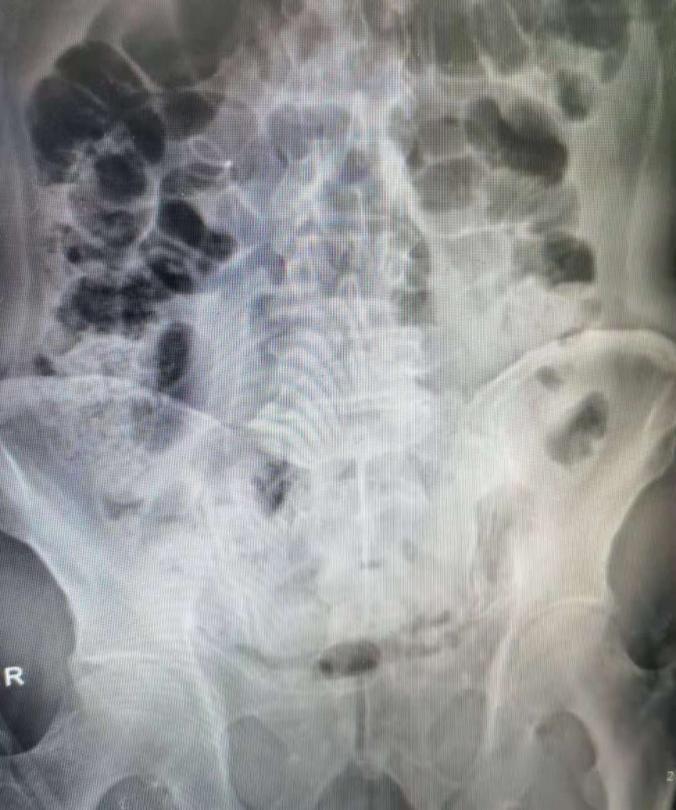

术后复查腹部立位片未见明显残石

本例患者的肾下盏结石术中使用新一代摩西激光击碎后均经负压取出,手术用时30分钟,未见明显出血及感染征像,未留置常规肾造瘘管(tubeless)。术后结石送成分分析,术后1天患者下地,2天拔除尿管,复查腹部立位片未见残石,嘱患者2-3周后拔除双J管,患者术后3天已顺利出院。此例手术亦为我院首例SMP示教病例, 对第二临床医学院在泌尿外科的实习同学进行示教,使其学习了解了泌尿外科结石领域的外科技术前沿。